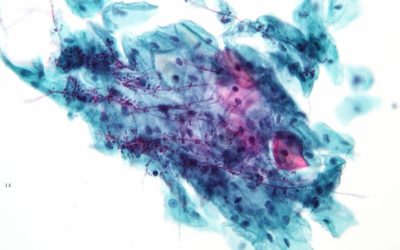

Candida albicans: Wissen zu Symptomen und mehr

Eine Mehrbelastung mit dem Hefepilz Candida im Darm zeigt sich vor allem durch Gedankennebel („brain fog“) und diverse Verdauungsbeschwerden.